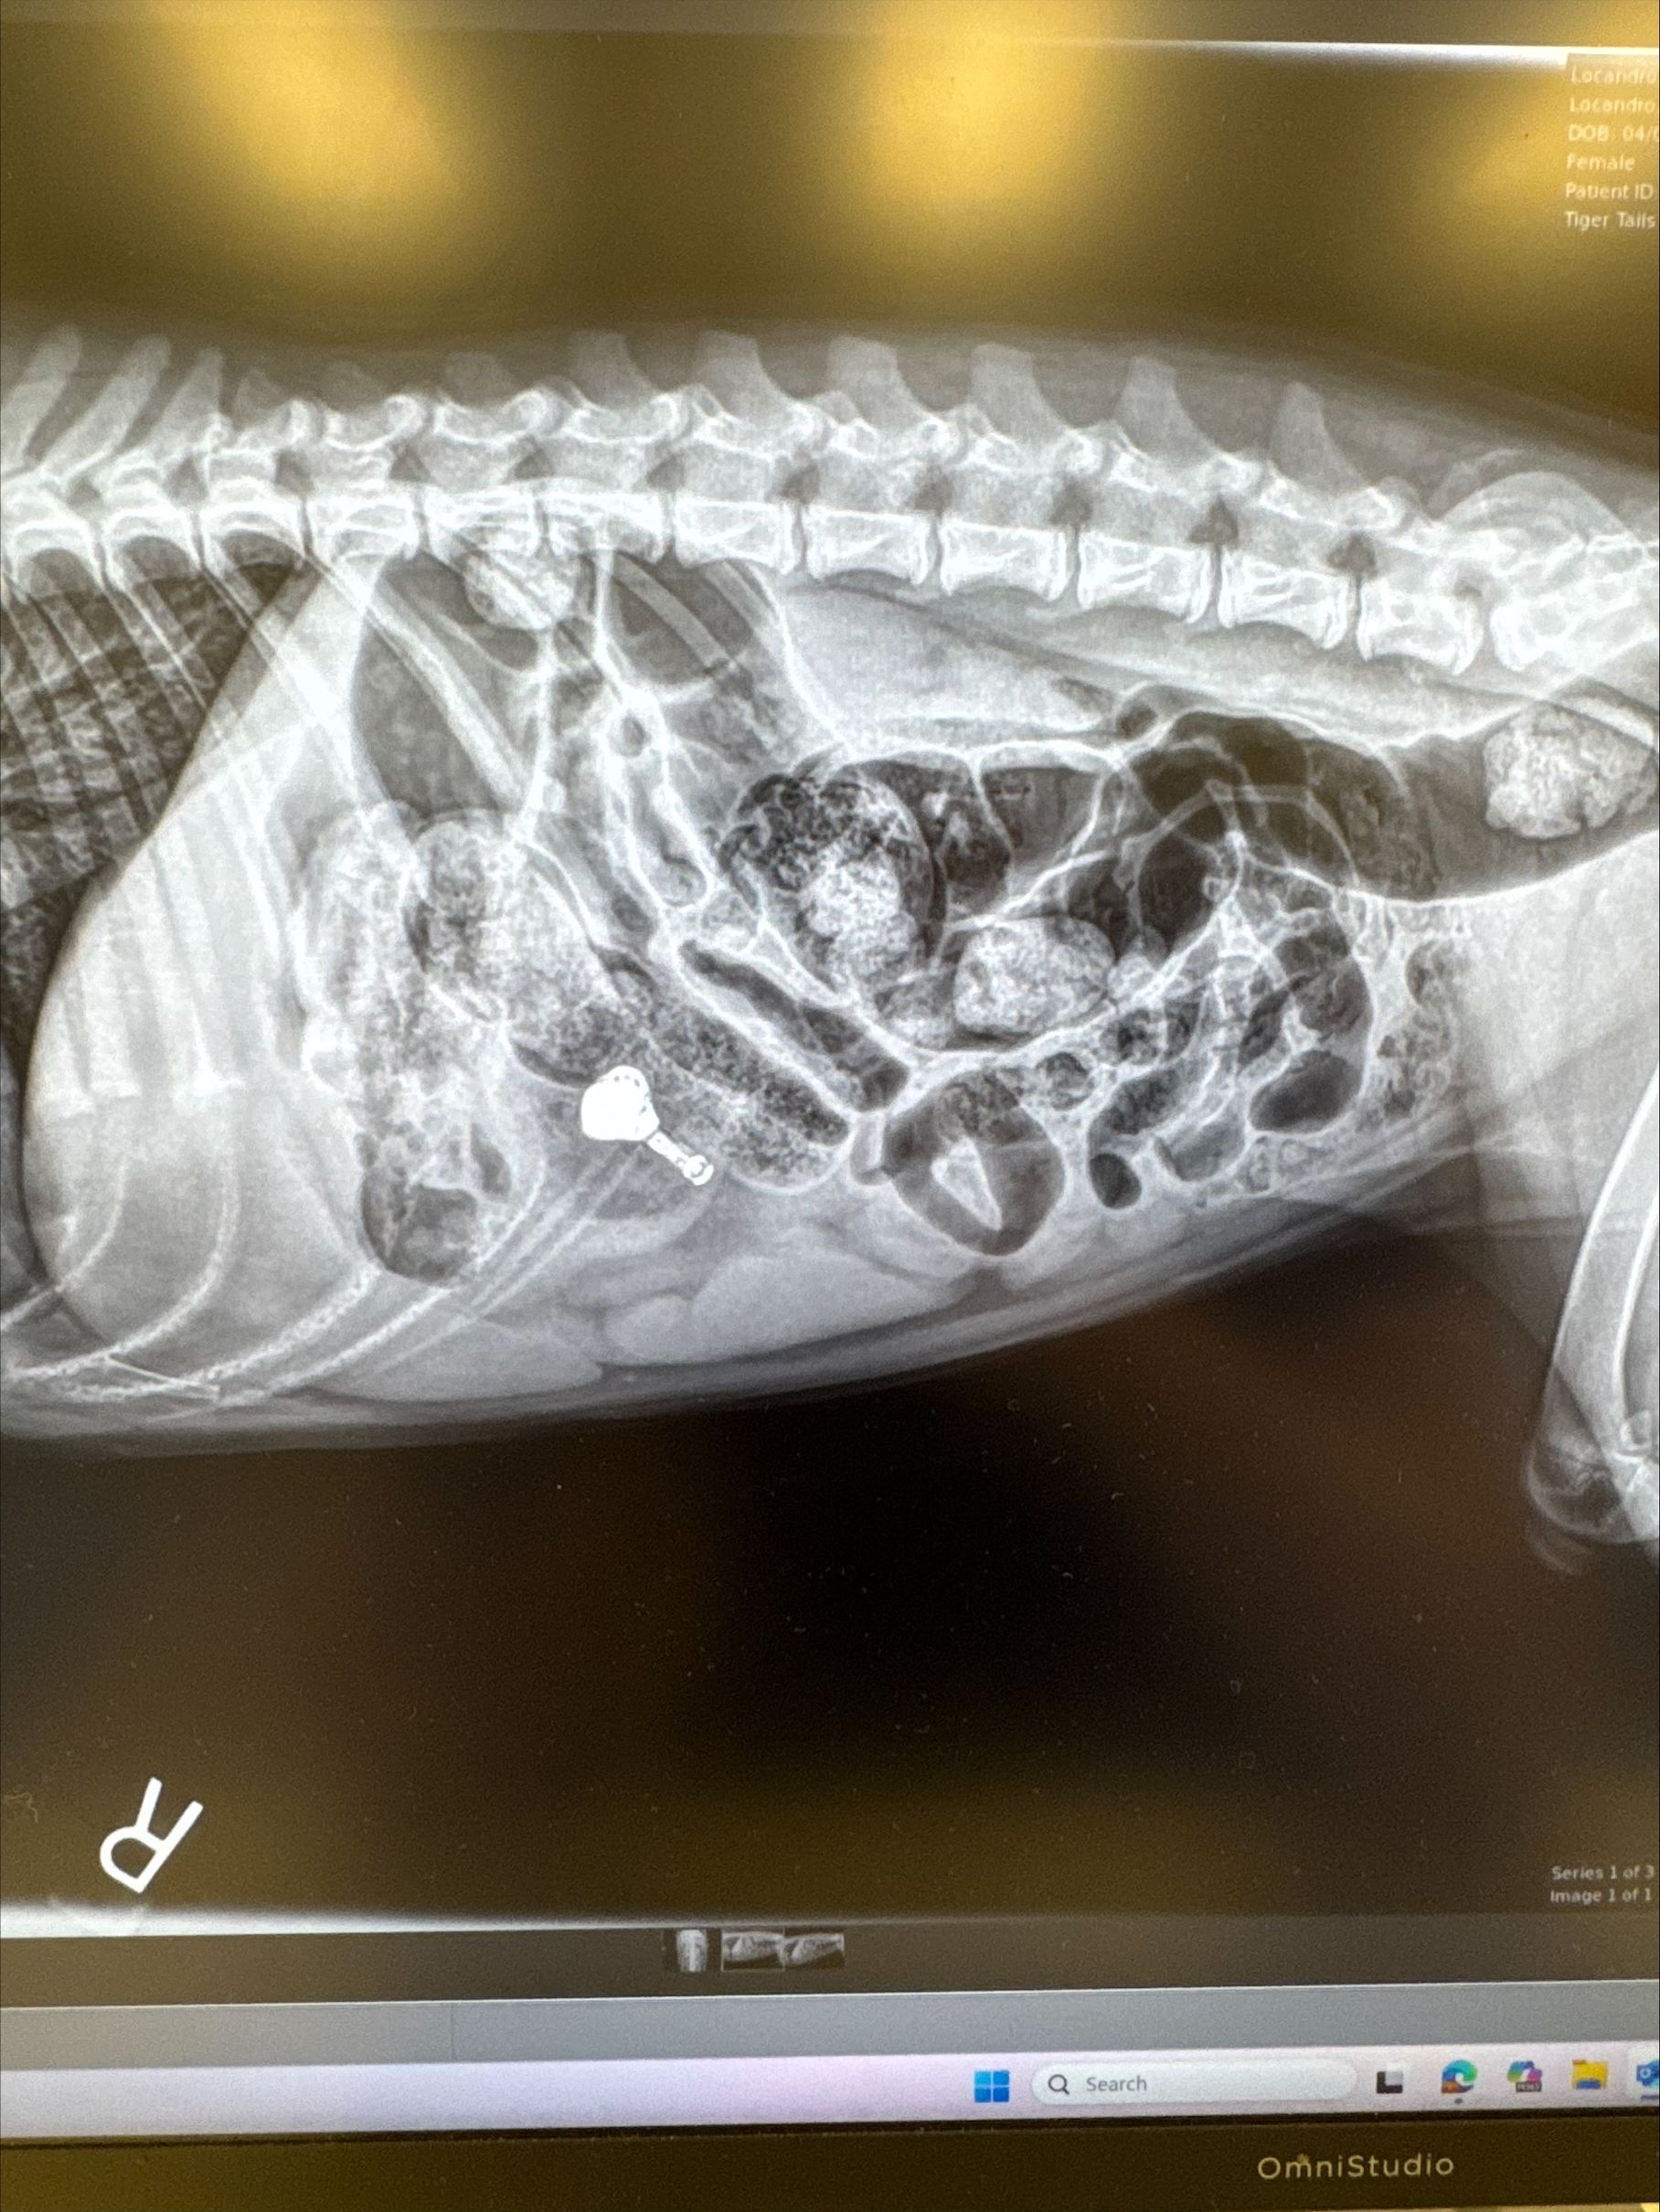

Radiographic Confirmation and Referral for Endoscopy

After 48 hours of monitoring, the AirPod had not passed. The owners brought the patient to their primary care veterinarian, where abdominal radiographs confirmed the AirPod remained in the stomach. She was promptly referred back to Ruby Veterinary Urgent Care for endoscopic retrieval.